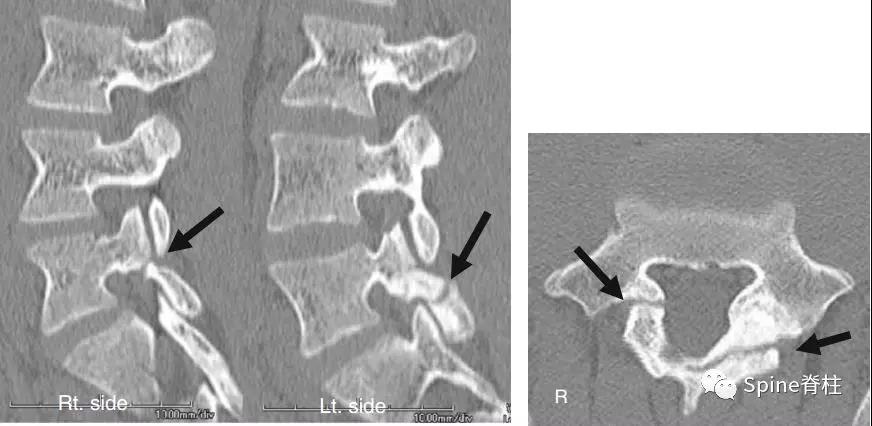

图:6个月复查可见右侧椎弓根裂已愈合(单箭头),但出现右侧峡部裂(双箭头)